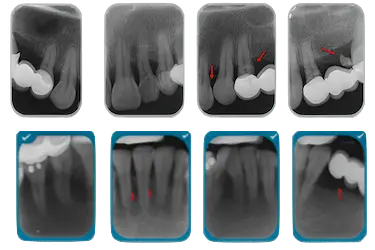

Un tratamiento de periodoncia comienza siempre con un estudio periodontal. En él tratamos de reconocer la situación y de realizar una valoración diagnóstica, para lo cual es necesario llevar a cabo una serie de radiografías y periodontograma.

Gracias a ambas pruebas, podemos determinar la ubicación, tamaño y profundidad de las bolsas periodontales, así como la pérdida de estructura ósea maxilar.

Como dijimos antes, el estudio periodontal está destinado a evaluar la situación de tus encías y a realizar el diagnóstico.

Para ello, nuestros periodoncistas te realizarán radiografías y un periodontograma, que consiste en la introducción de una sonda para determinar la gravedad de las bolsas periodontales y la pérdida de estructura ósea maxilar.